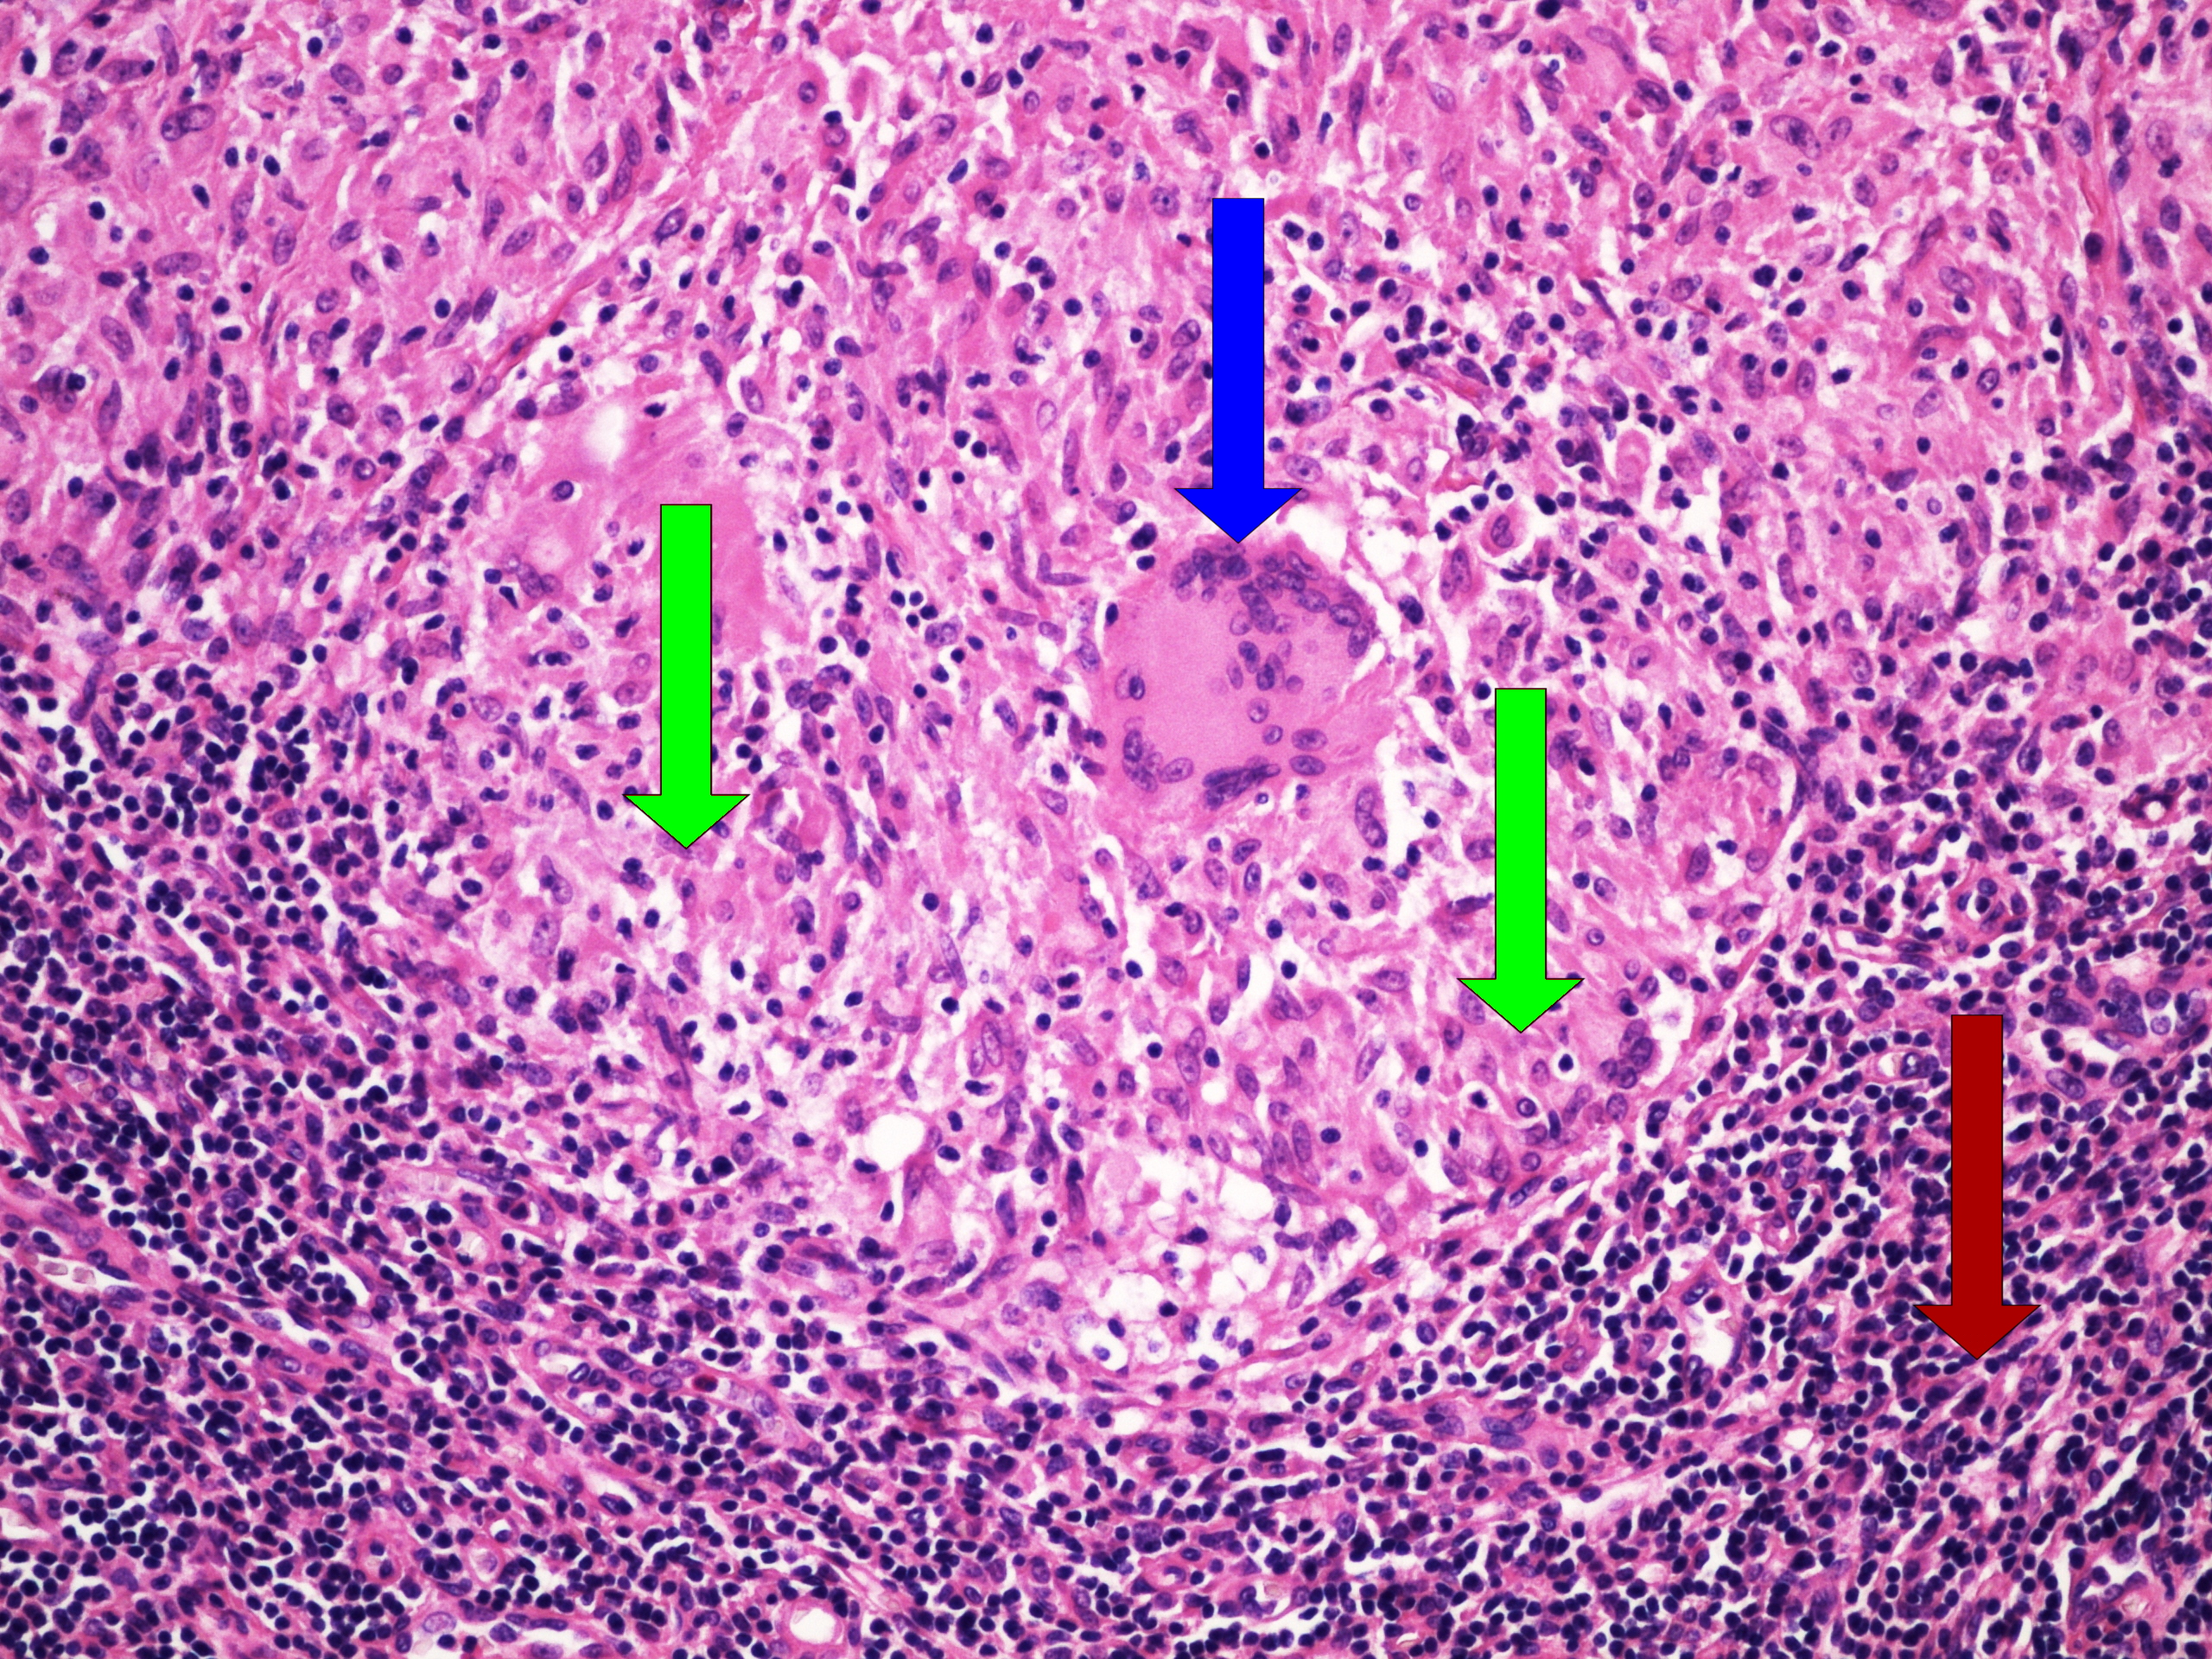

Preparát č.19 a č.20 - obrovskobuněčný granulom

Struktury

- cizorodý světlolomný materiál

- obrovské vícejaderné buňky